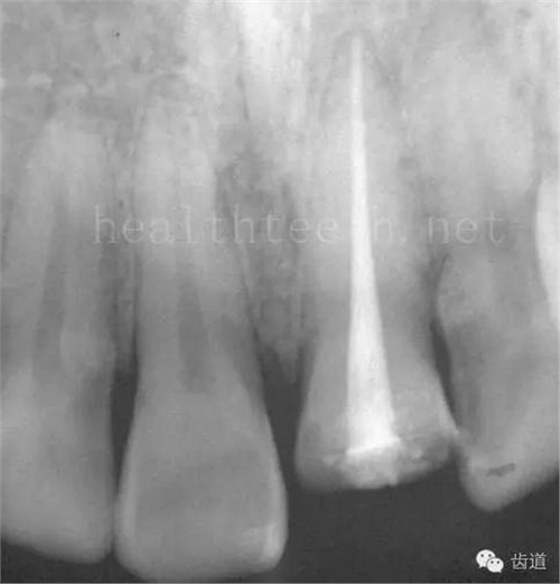

長期戴活動義齒不當或是戴不良修復(fù)義齒造成的口腔粘膜潰瘍,應(yīng)該引起高度警惕,因為這種潰瘍?nèi)菀装┳?/span> 黑毛舌 舌息肉,該患者同時伴有胃、食管息肉,后來看內(nèi)科了,具體情況不詳 四、孩子的牙齒問題 乳牙未退,牙根穿出牙齦對上唇粘膜造成刺激 乳牙滯留,也是孩子在退牙過程中最容易遇到的問題 五、牙齒發(fā)育上的問題 變色牙 氟斑牙 釉質(zhì)發(fā)育不全 四環(huán)素牙 牙神經(jīng)治療后的牙齒變色 10歲孩子剛剛萌出的牙齒變色 2、埋伏牙 左上乳3滯留,恒3未見萌出,曲面斷層片顯示牙齒埋伏 通過CT片確定埋伏牙齒具體的位置,顯示距離左側(cè)上頜竇很近,偏唇側(cè),這為手術(shù)定位提供了方便 手術(shù)中切斷、完整拔出,未損傷上頜竇 其他埋伏牙 3、多生牙 病例1 病例2 病例3,同時多生兩顆牙齒 4、各種畸形牙 畸形過小牙 融合牙:恒牙和乳牙都可以發(fā)生融合的情況(兩顆牙齒長在了一起) 畸形中央尖:在牙齒的中央,兩個牙尖之間又多長出一個牙尖,由于進食的磨耗很容易造成磨穿,神經(jīng)就會與外界相通,出現(xiàn)牙髓炎的癥狀 六、牙齒的外傷 牙冠折斷 牙根折斷 烤瓷牙打樁修復(fù)后牙根折斷 外傷后牙齒的全脫位,應(yīng)該保留牙齒盡早做再植手術(shù) 七、牙齒的慢性損傷 牙頸部楔狀缺損 牙冠劈裂及完整拔除后的情況 牙根縱裂及拔除后的情況 牙隱裂,牙齒表面有肉眼看不到的裂紋,細菌通過其進入牙髓,容易出現(xiàn)牙髓炎癥狀,嚴重可以造成牙齒的劈裂 這是一位來中國學(xué)習(xí)的俄羅斯大學(xué)生的牙齒,已經(jīng)做過了根管治療,牙齒咬合面有隱裂,通過鋼絲結(jié)扎固定,做鑄造金屬冠修復(fù)。 八、牙髓炎、根尖周炎 下面圖片都是慢性根尖周炎的病例,有了齲齒,進一步發(fā)展就是牙髓炎,如果此時沒有得到及時的治療,疾病會逐漸發(fā)展破壞到根尖的骨質(zhì),將骨質(zhì)破壞后就在牙齦上出現(xiàn)一個膿瘺,此時患者不再感覺到牙齒的疼痛了,往往忽視了治療,但是這種不痛并不是疾病好轉(zhuǎn)了,而是因為疾病的炎性滲出得到了引流,這個膿瘺會出現(xiàn)有時候變大了,有時候又變小了,但是如果不治療是不會自己愈合的,只有經(jīng)過完善的根管治療后才有好轉(zhuǎn)的可能,但是在疾病的治療中時間是起決定作用的,時間拖得越晚,好轉(zhuǎn)的可能性越小,經(jīng)過根管治療后如果膿瘺還是沒有消失,就需要做根尖刮治術(shù),如果仍然沒有好轉(zhuǎn),就只能做根尖切除術(shù)了,這對牙齒的穩(wěn)固是不利的。下面圖片中在膿瘺中插入了一個牙膠尖,是我們做根管充填用的材料,是非常軟的,就是在口腔牙齦瘺管的地方插進去,通過拍牙片可以清晰地看到它到達的位置,從而確定發(fā)病的牙齒,此處是為了讓大家看得更清楚。 門牙兩個膿瘺 烤瓷牙修復(fù)后牙齦出現(xiàn)兩個膿瘺,插入牙膠尖,牙片顯示牙膠尖到達的位置就是根尖炎癥的位置,根尖骨質(zhì)密度降低(發(fā)黑的地方) 牙齒根尖膿瘺,治療前、中、后的圖片對照,完善根管治療后膿瘺明顯消失了 牙髓炎和根尖炎治療的關(guān)鍵就是根管治療 合格的根管充填治療 不良的根管充填治療 九、關(guān)于智齒(第八顆牙) 四顆長不出來的智齒 智齒反復(fù)發(fā)炎造成的頰瘺,膿腫切開引流后面部會留疤 智齒造成的頜骨囊腫,手術(shù)切除后需要植骨 十、各種錯合畸形 開合 深覆合 深覆蓋,上頜前突 反合(地包天) 牙齒排列擁擠 來源:牙醫(yī)愛看的 KQ88口腔醫(yī)學(xué)網(wǎng)